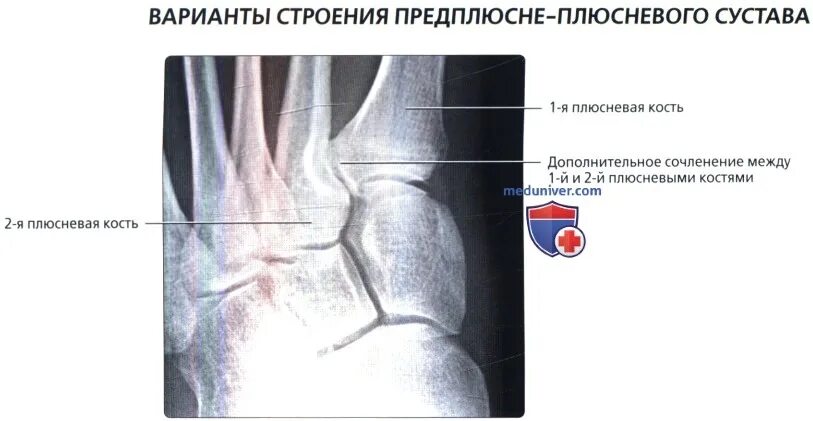

Не срастается сустав